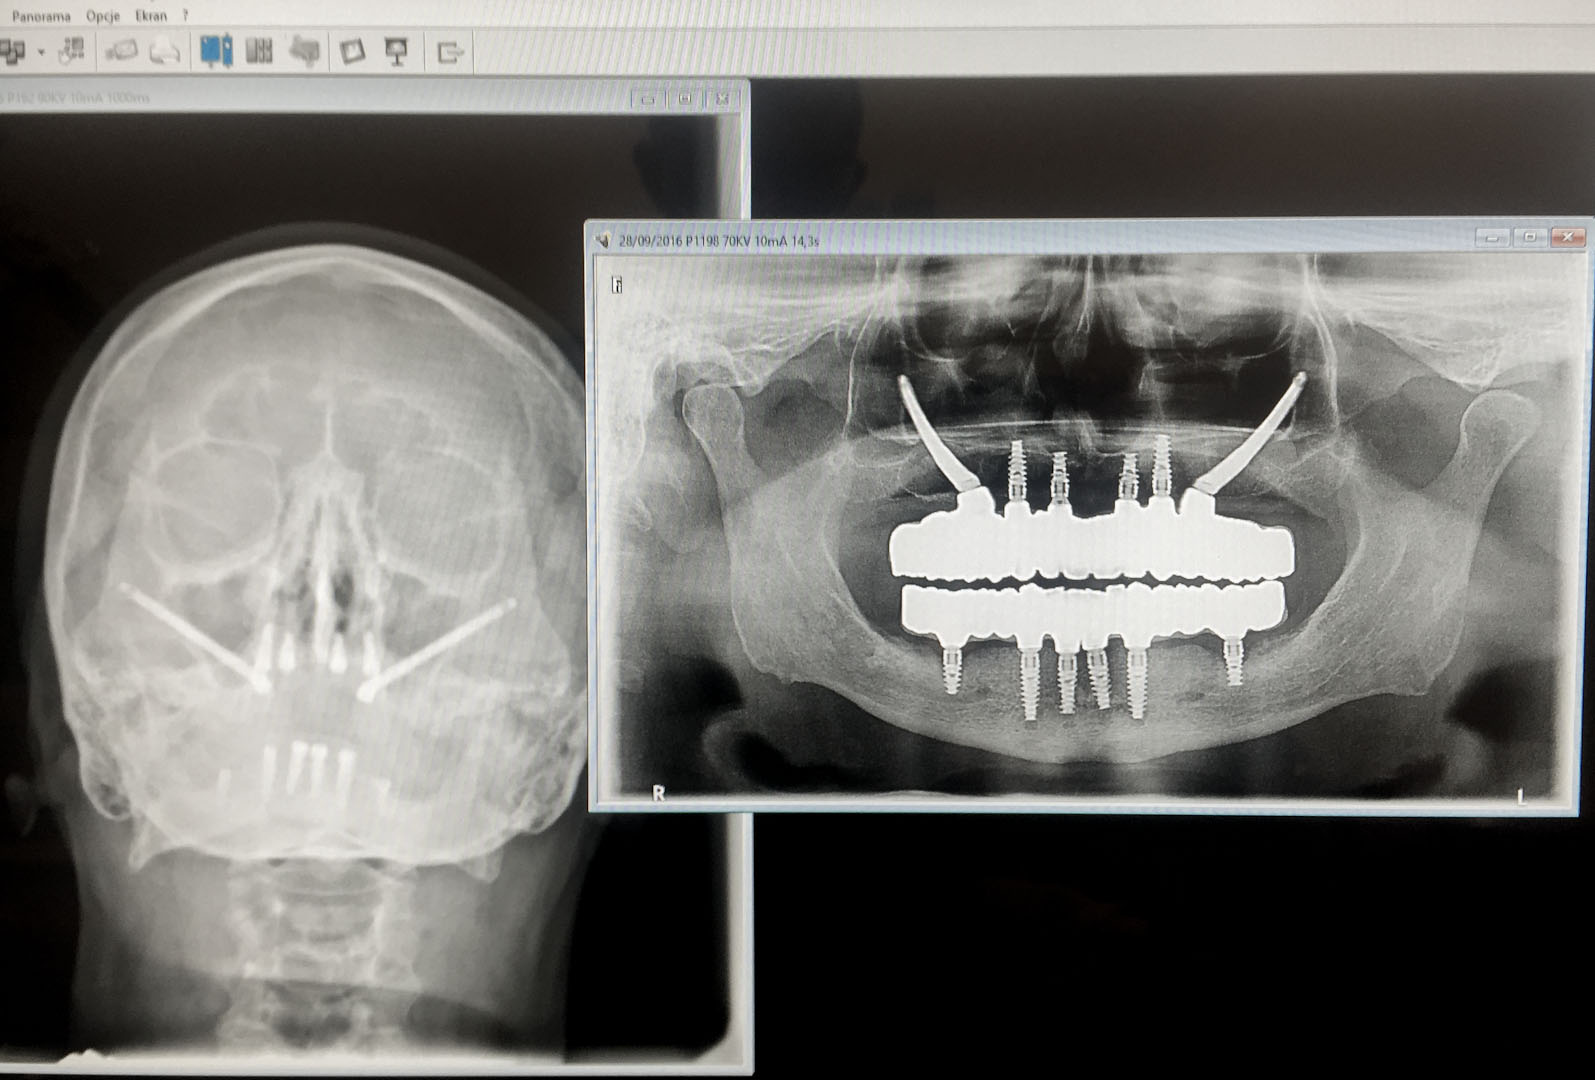

Zdjęcia pantomograficzne szczęk OPG – uwzględniają obraz wszelkich istotnych okolic ze szczególnym uwzględnieniem całości kości szczęk, zatok szczękowych oraz kości jarzmowych.

Tomografia komputerowa szczęk CT – ocenia stan i czystość zatok szczękowych, stopień skrzywienia przegrody nosa, drożność otworu zatoki szczękowej oraz anatomię tzw. zespołu ujściowo-przewodowego, od którego zależy długoterminowy efekt leczenia, kształt i wymiary kości jarzmowej.

Tomografia komputerowa stożkowa CBCT – ocenia wszystkie powyższe parametry anatomiczne, które przedstawia na trójwymiarowym obrazie.

Wymagana diagnostyka obrazowa, na podstawie której kwalifikujemy pacjenta do zabiegu wszczepienia implantów Zygoma, to:

RTG OPG jako podstawowe badanie radiodiagnostyczne

CBCT, które wybiórczo może okazać stan kości w pozostałej części zębodołowej szczęk, stan oraz powietrzność zatok szczękowych, co jest istotnym parametrem kwalifikującym pacjenta do zabiegu operacyjnego, stan przegrody nosa

CT tomografia komputerowa liniowa ukazująca stan całości zatok okołonosowych, drzewo małżowinowe, stopień skrzywienia przegrody nosa, stopień obturacji naturalnego otworu łączącego jamę nosa z zatoką szczękową – rozworu zatoki szczękowej.